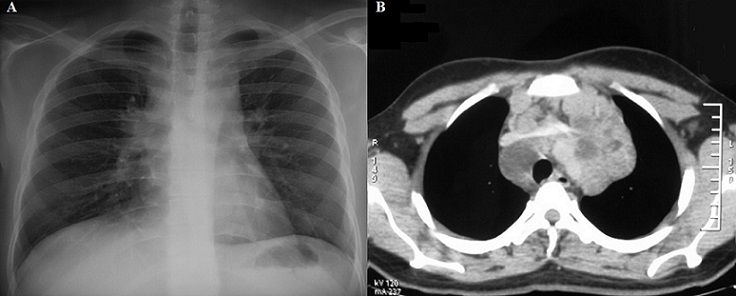

A 32-year-old man, with no history of cigarette smoking, had four weeks history of non productive cough, chest pain and myalgias. Physical examination revealed a painless bilateral cervical lymphadenopathy, the respiratory examination was normal. Chest radiography showed an enlarged upper and middle mediastinum (A). Computed tomography (CT) of the thorax showed a large and non homogeneous mass in the anterior and middle mediastinum and a small pericardial effusion, with displacement of vascular structures (B). Laboratory analysis revealed an elevated lactate dehydrogenase level of 690 IU per liter. The exicional biopsy of the left cervical lymph node revealed a caseating and necrotizing granulomatous lesions and confirmed a diagnosis of lymph node tuberculosis. The biopsy of the right cervical lymph node established a B-cell non-Hodgkin lymphoma, and so a rare association with tuberculosis. The patient received anti-tuberculosis therapy. The regimen was based on two months of ethambutol, rifampicin, pyrazinamide and isoniazid, followed by four months of rifampicin and isoniazid. He received also chemotherapy with cyclophosphamide, adriamycin, vincristine and prednisolone. The patient presented, two months later with clinical and radiographic improvement.